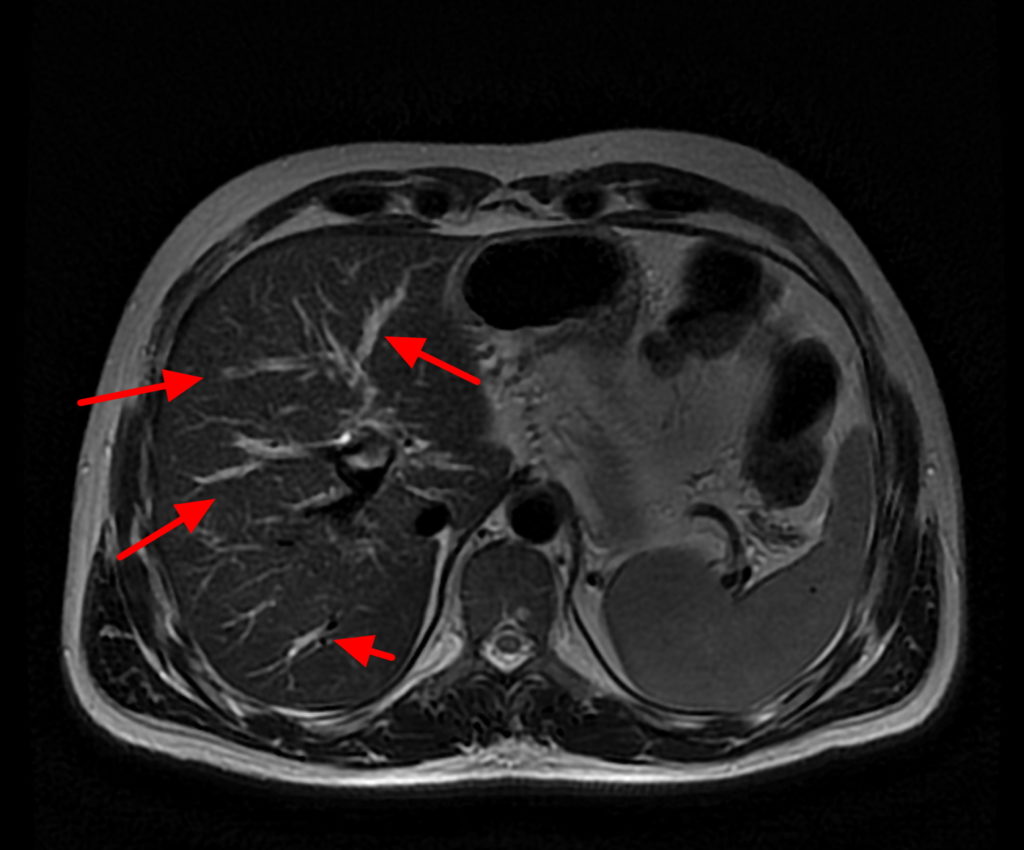

Web primary sclerosing cholangitis (psc) is a chronic and progressive cholestatic liver disorder of unknown etiology. The bile duct system carries bile from the liver and gallbladder into the first. Web primary sclerosing cholangitis (psc) is a chronic, progressive disease of the bile duct system. Bile ducts carry the digestive liquid bile from your liver to your. Web primary sclerosing cholangitis (psc) is a disease of the bile ducts. It causes chronic inflammation in your bile ducts (cholangitis), which eventually causes scarring.

Web primary sclerosing cholangitis (psc) is a chronic, progressive disease of the bile duct system. Web primary sclerosing cholangitis (psc) is a disease of the bile ducts. Web primary sclerosing cholangitis (psc) is a chronic, progressive disease of the bile duct system. It causes chronic inflammation in your bile ducts (cholangitis), which eventually causes scarring. The bile duct system carries bile from the liver and gallbladder into the first. Bile ducts carry the digestive liquid bile from your liver to your. Web primary sclerosing cholangitis (psc) is a chronic and progressive cholestatic liver disorder of unknown etiology.